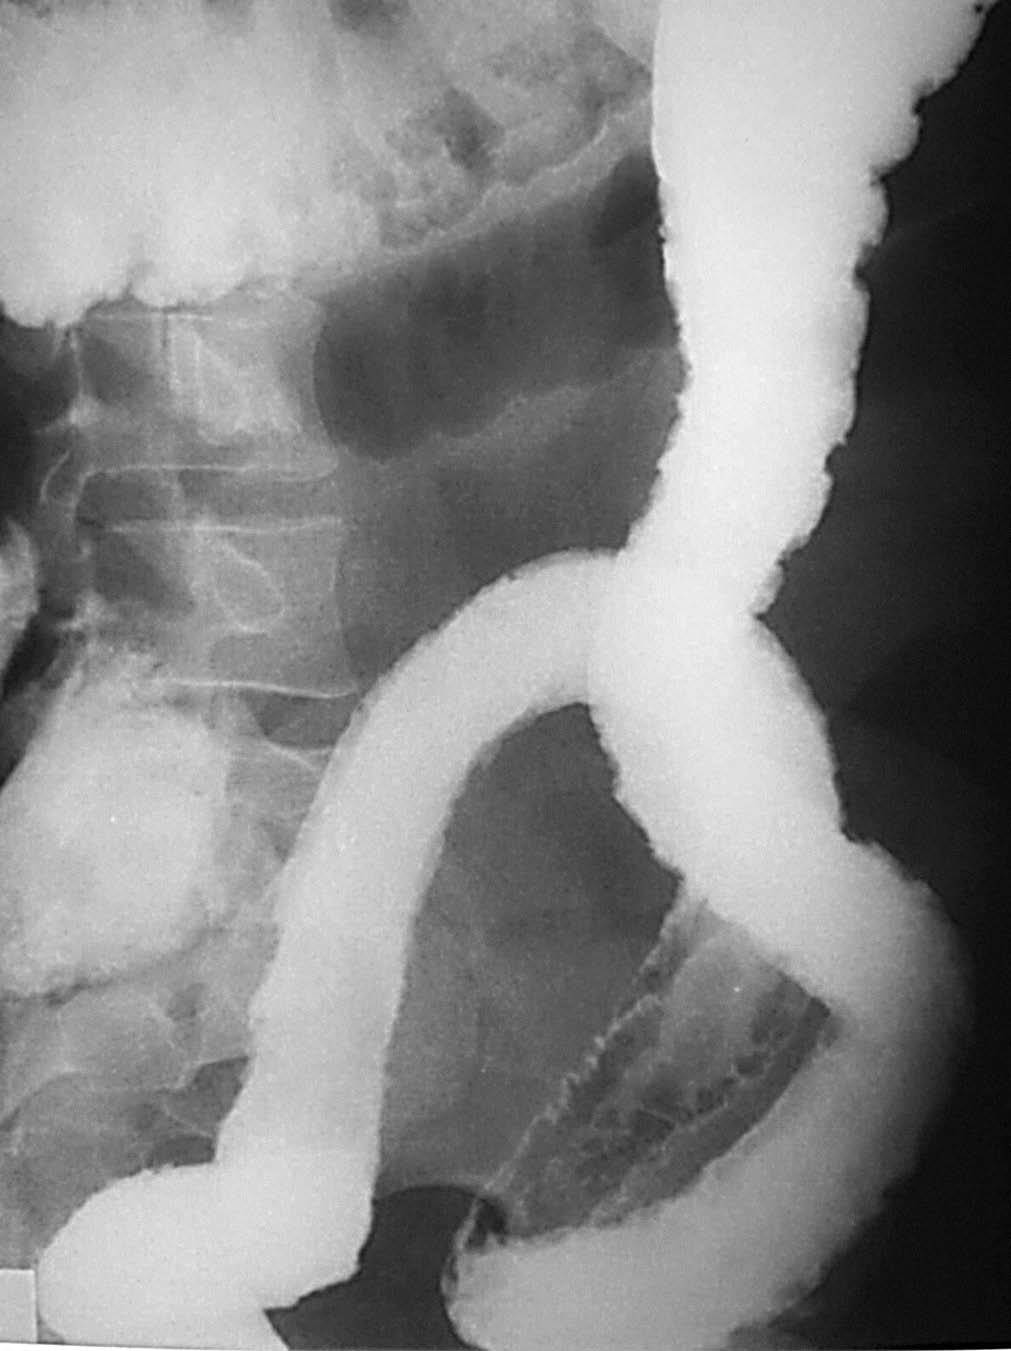

El aspecto final de la CU se caracteriza por la apariencia rígida del colon, por la contracción mantenida de la muscularis mucosa que justifica esa pérdida de la haustración (es el colon en "tubería de plomo" [fig. 14]) y el aspecto atrófico de la ampolla rectal20. El característico signo del "halo graso", depósito de grasa al nivel de la submucosa, se ve también en las situaciones de EII, aun cuando se define como más propio de la CU13,22. También es típico el aumento de la distancia recto-sacra, estando esa zona ocupada por grasa con un componente inflamatorio, con edema, y la presencia de pequeñas imágenes correspondientes a ganglios linfáticos.

Fig. 14.--Aspecto final de la colitis ulcerosa con esa apariencia rígida, carente de haustración por la contracción mantenida de la muscularis mucosa.